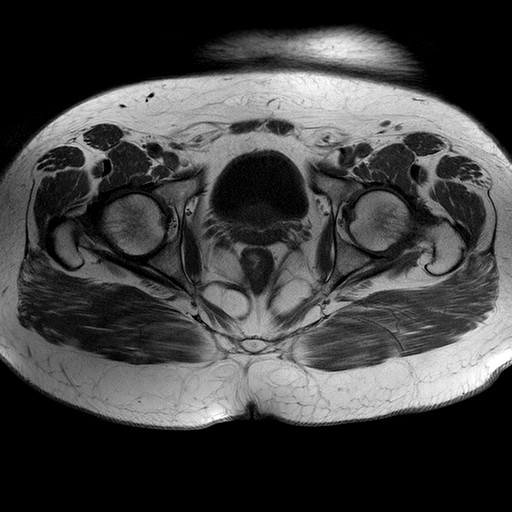

Esami: RMN BACINO

Evidenti e simmetriche alterazioni osteofitosiche in regione coxo femorale con riduzione delle rime articolari. Degenerazione completa del cercine glenoideo. Non attuali segni di versamento articolare. Non segni di edema osseo che escludono attuale algodistrofia od osteonecrosi. Lieve e simmetrica riduzione del trofismo della muscolatura glutea.